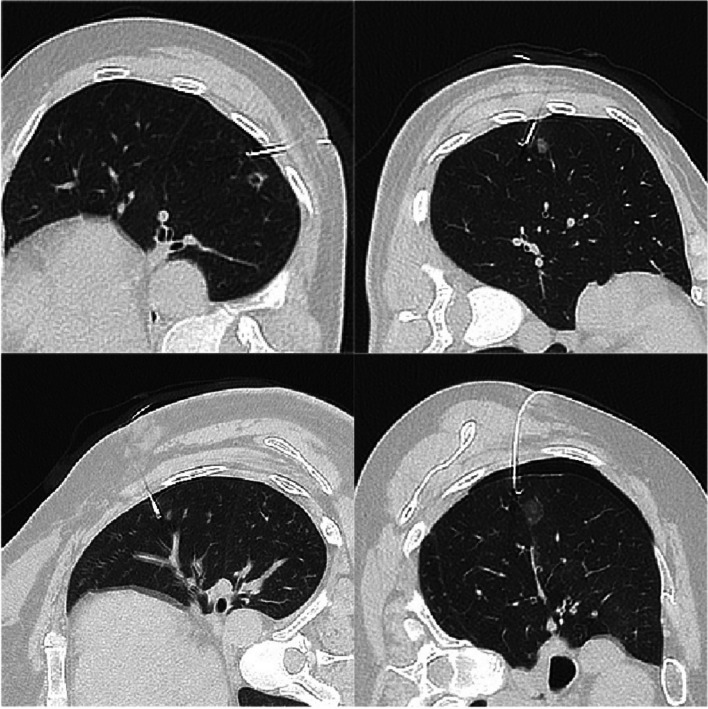

Fig. 4.

CT scanning was performed after the localization to confirm the accuracy